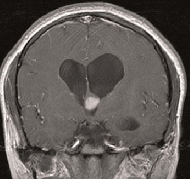

位于三腦室的神經(jīng)節(jié)細(xì)胞膠質(zhì)瘤能通過(guò)手術(shù)切除嗎?

神經(jīng)節(jié)細(xì)胞膠質(zhì)瘤是一種少見(jiàn)的生長(zhǎng)緩慢的中樞神經(jīng)系統(tǒng)腫瘤,由膠質(zhì)成分和分化的神經(jīng)元組成...